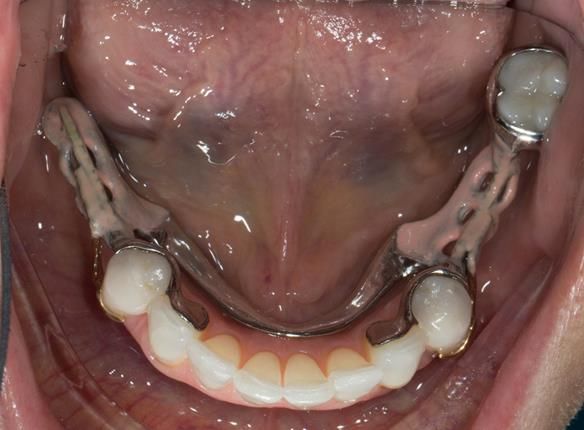

This newsletter describes in step by step detail Angela's transition through immediate partial dentures to crown supported definitive metal based dentures.

The clinical situation and treatment process is shown in detail below with photographs. I (Finlay Sutton) provided the clinical work and Rowan Garstang provided the technical work.